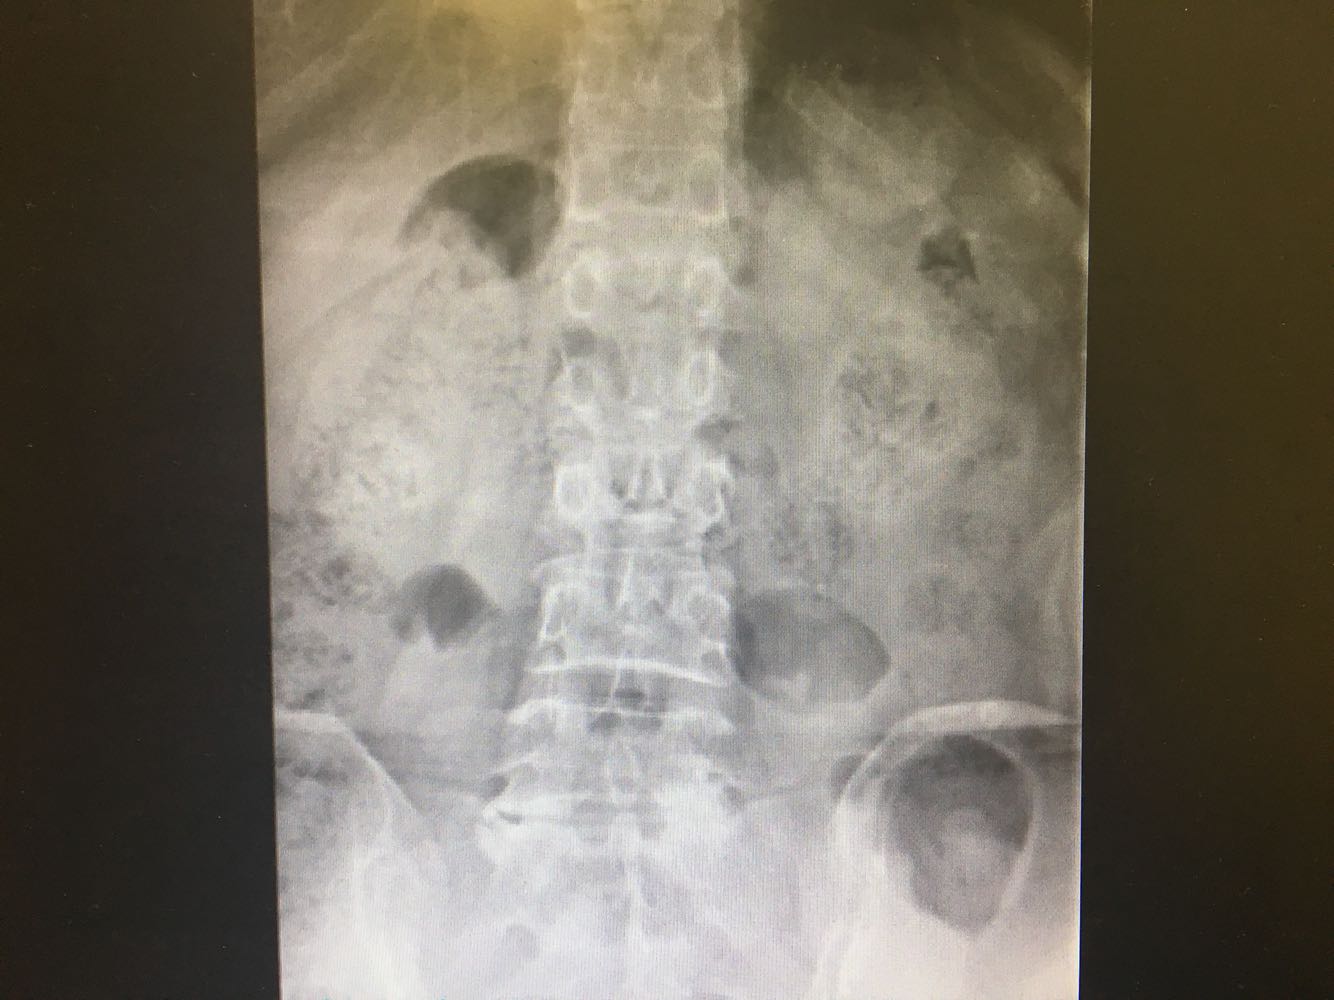

患者,女性,54岁 主诉:摔伤致腰背疼痛伴活动受限3小时 现病史:患者于3小时前于摔倒致腰背疼痛伴活动受限,患者诉站立及坐位时腰痛加剧,卧床时可缓解,否认头晕头痛、恶心呕吐等不适,遂至我院就诊,查X片示:腰椎L1压缩性骨折,现为进一步诊治收治入院,发病以来,神清,精神可,胃纳夜眠可,二便无殊,体重无明显变化。

查体:脊柱无侧弯、畸形,腰段压痛及叩击痛阳性,下肢肌力肌张力正常,运动及感觉正常。 辅检:见现病史

诊断:腰椎骨折(L1) 治疗:完善术前检查后行手术治疗